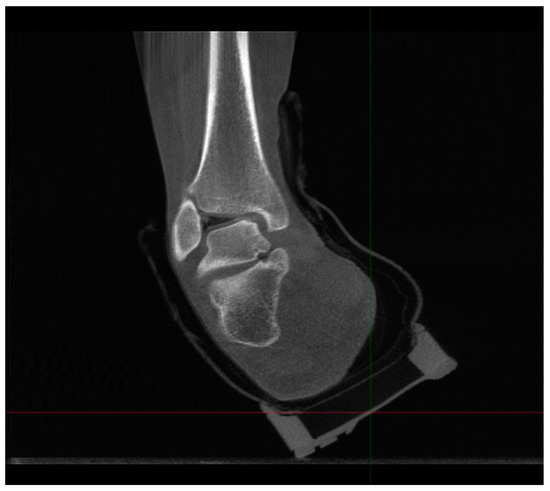

4.2.1. Description of Techniques for Image Acquisition